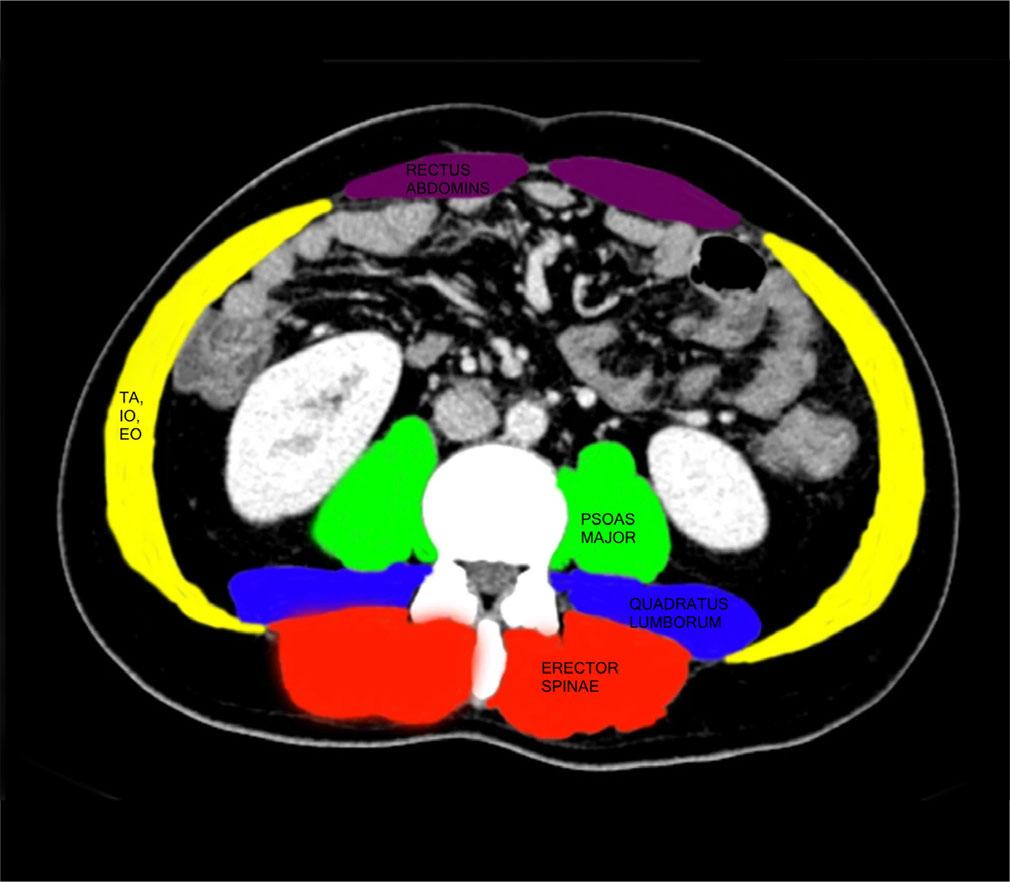

The L3-SMI was calculated from the abdominal CT scan by analyzing a single axial slice at the level of the third lumbar vertebra (L3) (Fig. 2). This region was chosen because it strongly correlates with whole-body muscle mass. Skeletal muscles, including the psoas major, paraspinal muscles (erector spinae and quadratus lumborum), and abdominal wall muscles (rectus abdominis, EO, IO, and TA) were identified and segmented. To differentiate muscle from fat and other tissues, a Hounsfield unit (HU) range of −29 to +150 HU was applied. The total cross-sectional skeletal muscle area (cm2) at L3 was measured using specialized imaging software. L3-SMI was then determined by normalizing this muscle area to the patient’s height squared (m2) using the formula: L3-SMI = Skeletal Muscle Area (cm2) / Height2 (m2). Established thresholds were used to define sarcopenia: less than 42 cm2/m2 for males and less than 38 cm2/m2 for females(8).

Measurement of L3-SMI (Colors represent the following muscles: purple – rectus abdominis; green – psoas major; red – erector spinae; blue – quadratus lumborum; yellow – abdominal wall muscle)